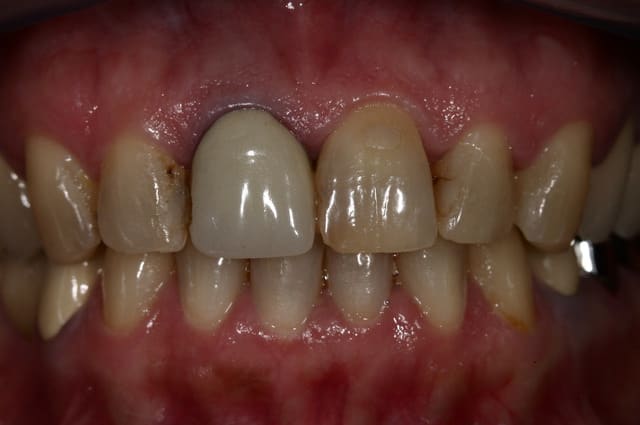

Ce sont toujours des cas un peu frustrant. La racine est difficilement "eclaircissable".

On parviens en général a limiter l'effet grisatre, sans le faire disparaitre complètement.

un exemple en photo.

T'aurais peut être gagné en integration en remontant ta limite de preparation, éliminant de la gencive colorée et alignant le contour gingival par la même occasion mais joli cas neanmoins.

très juste, je m'en rend plus compte sur les photos !

ok pour la chir, mais surtout pour aligner les collets. La racine se voit assez haut...

De toute façon un cas comme ça, il faut laisser maturer la gencive au moins quelques mois... je vous remets des photos dans 6 mois (là on est à 1 semaine après la pose)